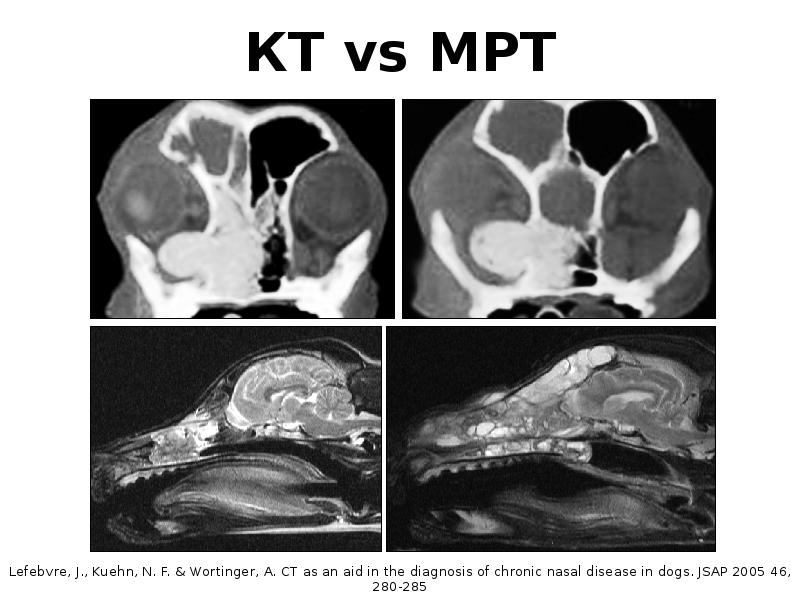

Компьютерная томография в неврологии презентация - 86 фото